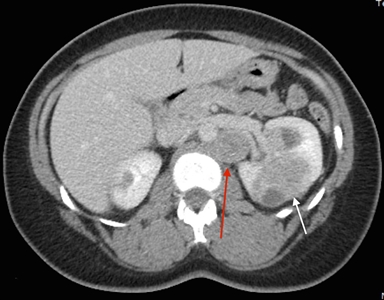

Los síntomas del cáncer de células renales (RCC) son hematuria, dolor lumbar y masa palpable. Sin embargo, muchas personas con RCC son asintomáticas. Además, no todas las personas con HLRCC presentarán RCC, ni será parte del cuadro clínico inicial. La mayoría de los RCC son unilaterales y solitarios; pero en algunas personas, son multifocales. Todavía no se ha determinado el incidencia exacta del RCC en personas afectadas, las estimaciones realizadas por diferentes grupos oscilan mucho (1–60 %).[1,3,8] La incidencia varía en función del lugar donde se realizó el estudio, las pautas de derivación de grupos individuales, y los exámenes de detección para el RCC a los que se someten los participantes. En los estudios del Instituto Nacional del Cáncer (NCI), se identificó RCC en el 32 % de las familias evaluadas.[1,3] La mediana de edad en el momento de la detección del RCC fue de 37 años,[9] aunque se notificaron algunos casos en edades tan tempranas como 10 años.[10] En otra serie grande de 135 pacientes se calculó que el riesgo de por vida fue de un 20,8 % a los 85 años de edad.[11] A diferencia de otros síndromes hereditarios de RCC, el RCC asociado a la HLRCC es muy maligno,[12,13] con un grado nuclear de Fuhrman de 3 o 4 en muchos casos; 9 de 13 personas murieron por enfermedad metastásica en el transcurso de 5 años del diagnóstico.[3] En la Figura 1 se observan varias lesiones de RCC en un paciente con HLRCC.

Vista de un corte transversal del cuerpo en donde se observan tumores en ambos riñones. Hay un tumor más pequeño en el riñón izquierdo y un tumor más grande en el riñón derecho. Junto al tumor más grande, se observa un ganglio peritoneal.